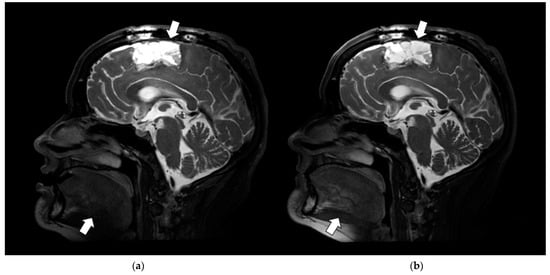

3.3.4. SNR and Anatomic Conspicuity

3.3.5. Image Uniformity and Depiction of Fine Anatomic Detail